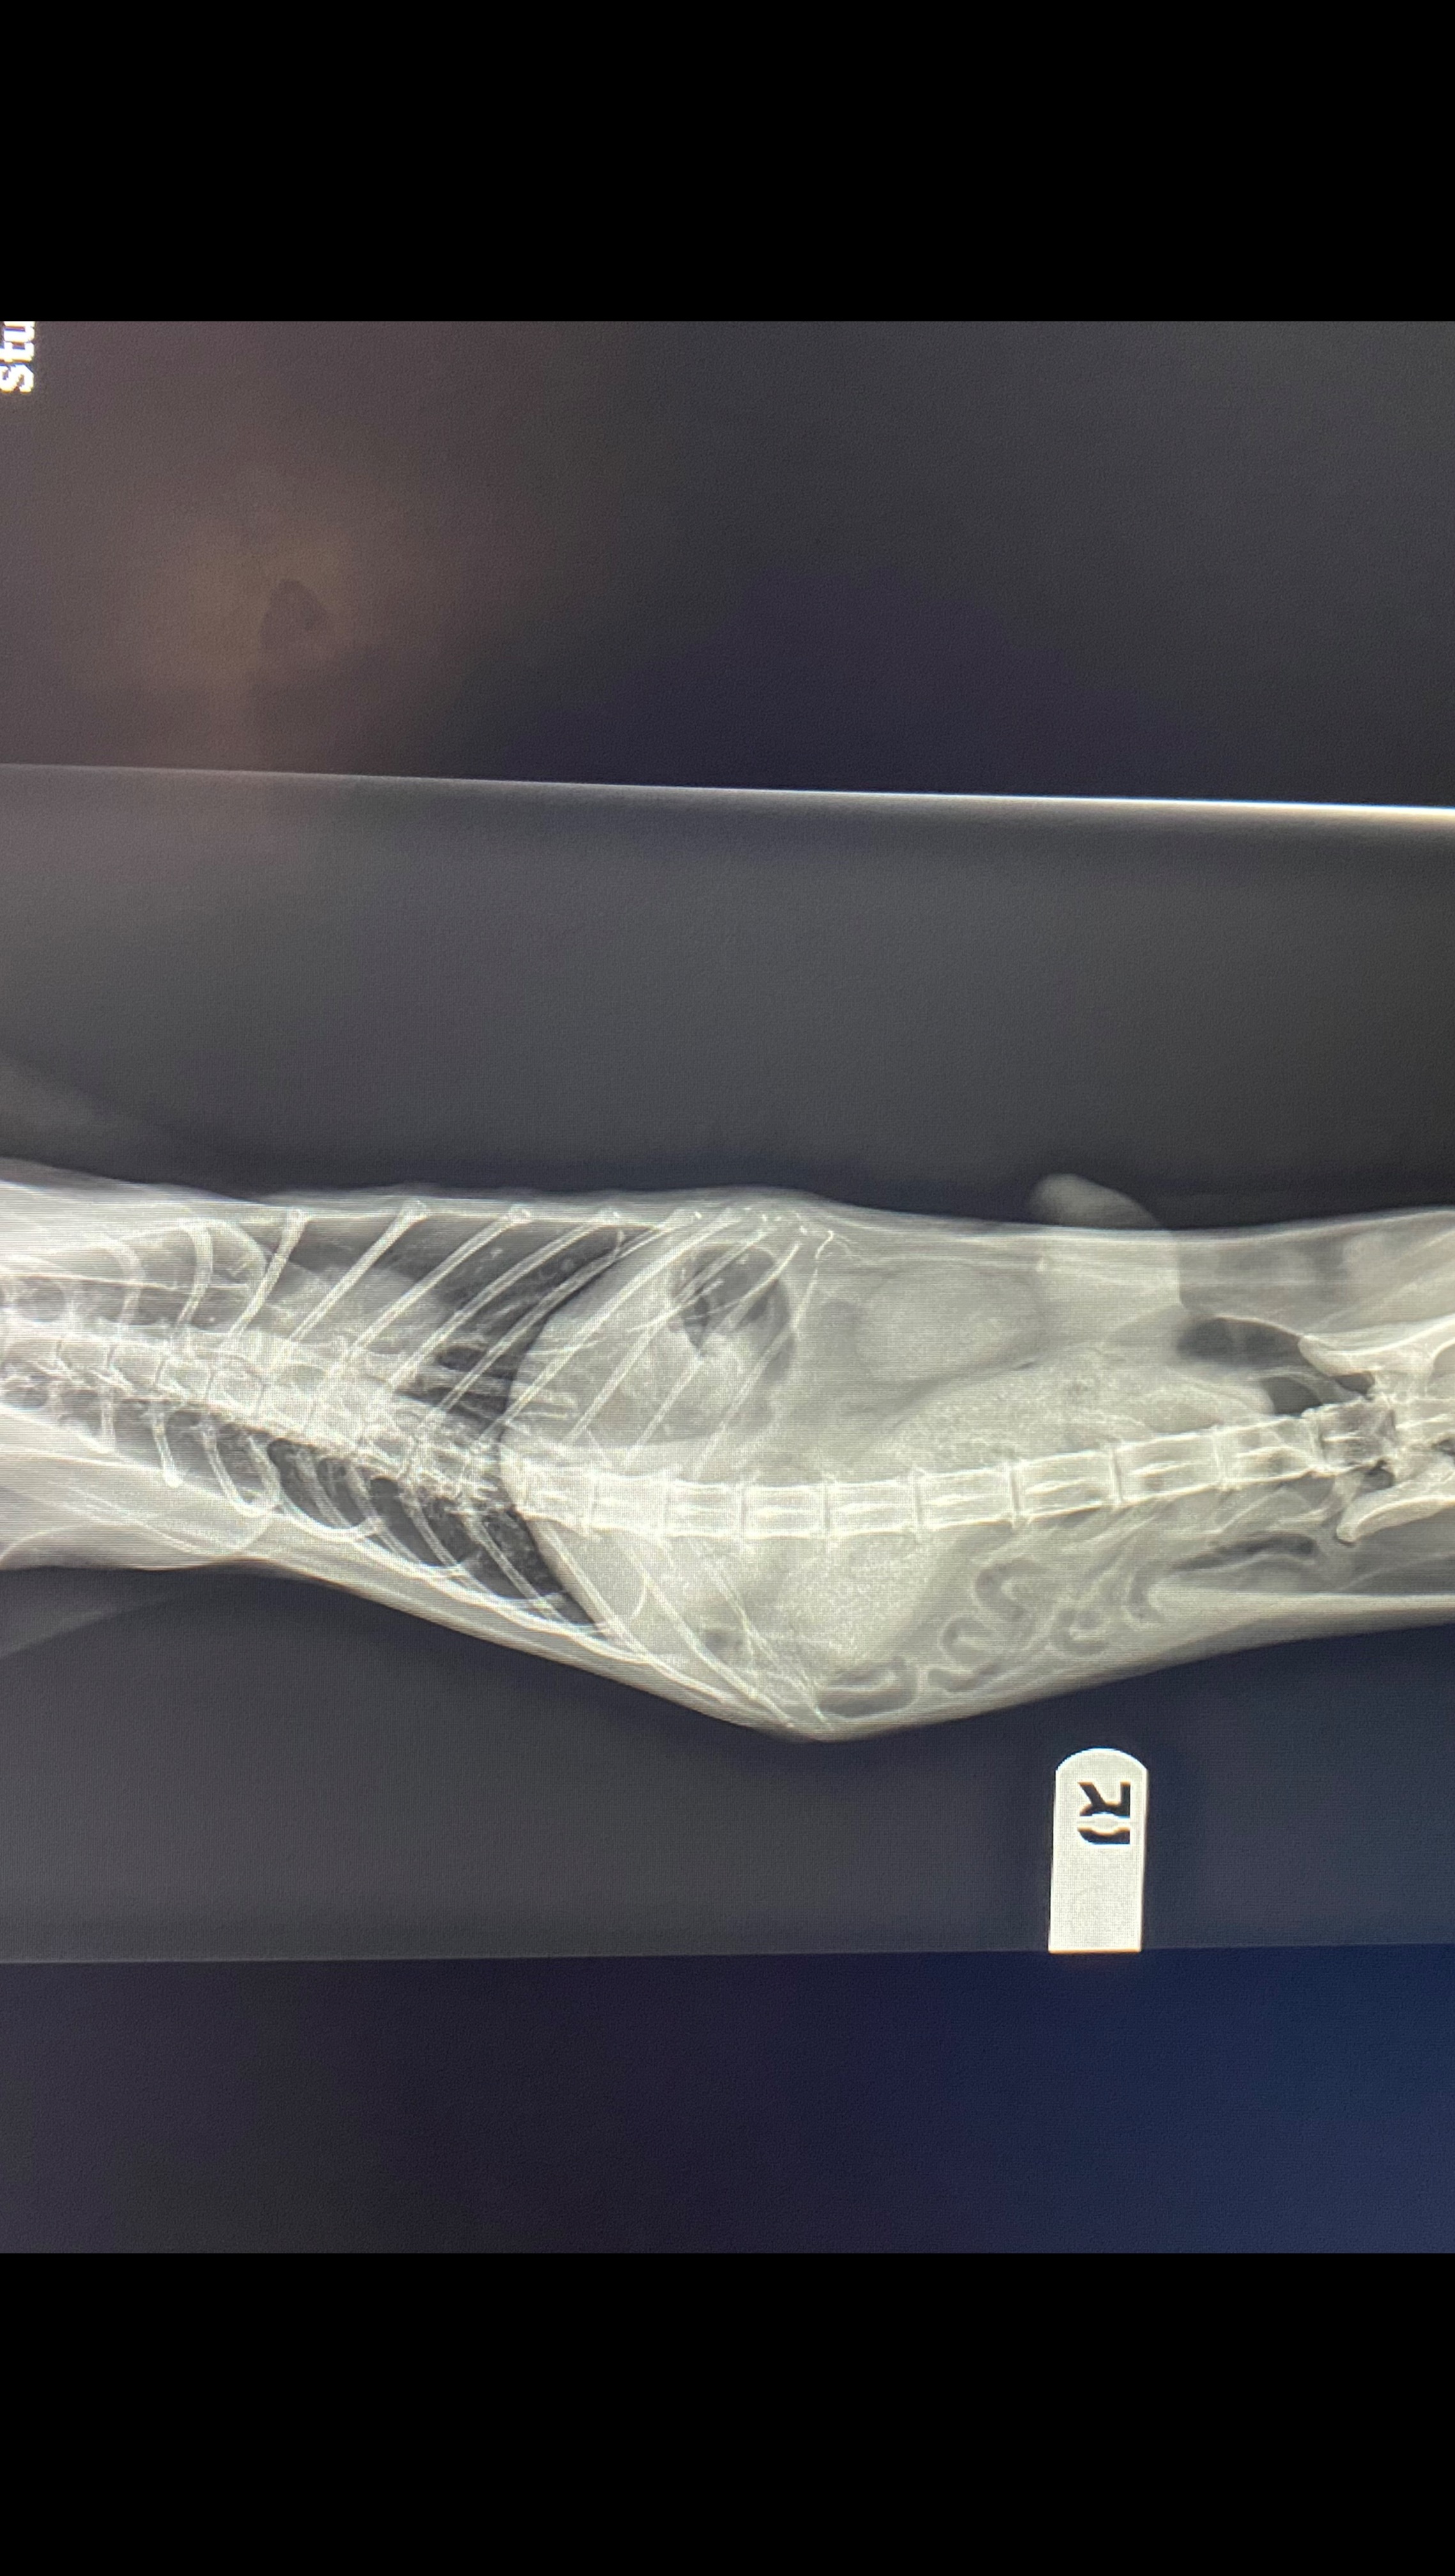

Donation protected